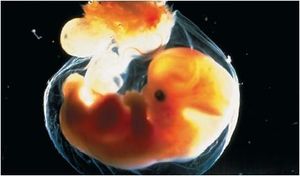

المضغة بالانجليزية Embryo ، باليونانية ἔμβρυον ، وهو طور من مراحل تطور الجنين في الإنسان ، ويكون في الفترة من بداية الإخصاب حتى نهاية الأسبوع الثامن من الحمل.

يأتي طور المضغة بعد مرحلتي النطفة و العلقة ، ويبدأ بظهور الكتل البدنية في اليوم الرابع والعشرين أو الخامس والعشرين في أعلى اللوح الجنيني ، ثم يتوالى ظهور هذه الكتل بالتدريج إلى مؤخرة الجنين. وفي اليوم الثامن والعشرين يتكون الجنين من عدة فلقات تظهر بينها انبعاجات ، مما يجعل شكل الجنين شبيهاً بالعلكة الممضوغة. ويزداد اكتساب الجنين في تطوره شكل المضغة تدريجياً من حيث الحجم بحيث يكتمل هذا الطور في بقية الأيام الأربعين الأولى من حياته ، وينتهي هذا الطور بنهاية الأسبوع السادس.

يحدث بعد ذلك تغير لأوضاع الجنين نتيجة تحولات في مركز ثقله مع تكون أنسجة جديدة ، ويشبه ذلك تغير وضع وشكل المادة حينما تلوكها الأسنان. وكما تستدير المادة الممضوغة قبل أن تبلع، فإن ظهر الجنين ينحنى ويصبح مقوساً شبه مستدير مثل حرف (C) بالإنجليزية. يكون طول الجنين حوالي 1 سم في نهاية هذه المرحلة ، لأن جميع أجهزة الإنسان تتخلق في مرحلة المضغة ولكن في صورة برعم ويكون طول الجنين في مرحلة المضغة ما يقارب 1 سم.

ويبدأ ظهور بعض الأعضاء ، كالعينين و اللسان وذلك في الأسبوع الرابع في مرحلة المضغة و الشفتين في الأسبوع الخامس ، ولكن لا تتضح المعالم إلاّ في نهاية الأسبوع الثامن. وتظهر نتوءات الأطراف اليدين و الساقين في هذا الطور. كذلك يمكن بسهولة تميز بروز القلب. ويعتبر الذيل المنحني باتجاه البطن وبما يحمله من الفلقات من الملامح المميزة لهذه المرحلة.